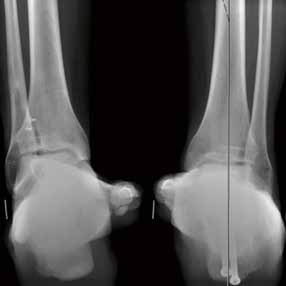

Als nächster Schritt sollte dann eine eingehende klinische Untersuchung durchgeführt werden. Man beginnt mit der Inspektion, wobei Lokalisation und Ausdehnung von Schwellung und Hämatomverfärbung erfasst werden (Abb. 1).